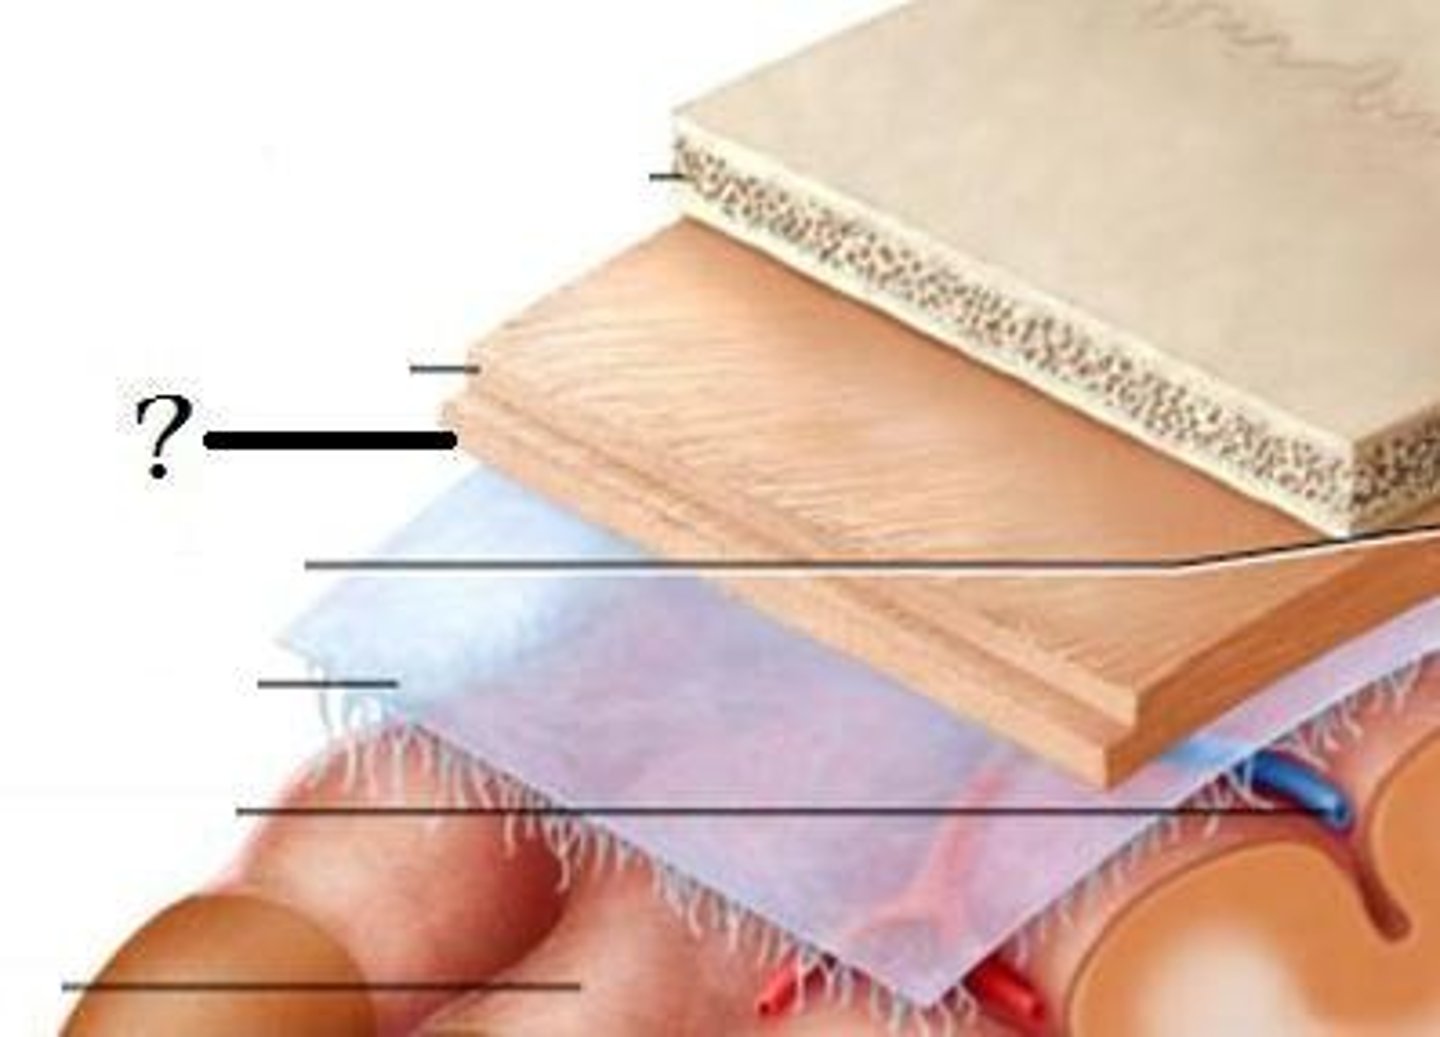

Dura mater

What is this?

Arachnoid mater

What is this?

pia mater

What is this?